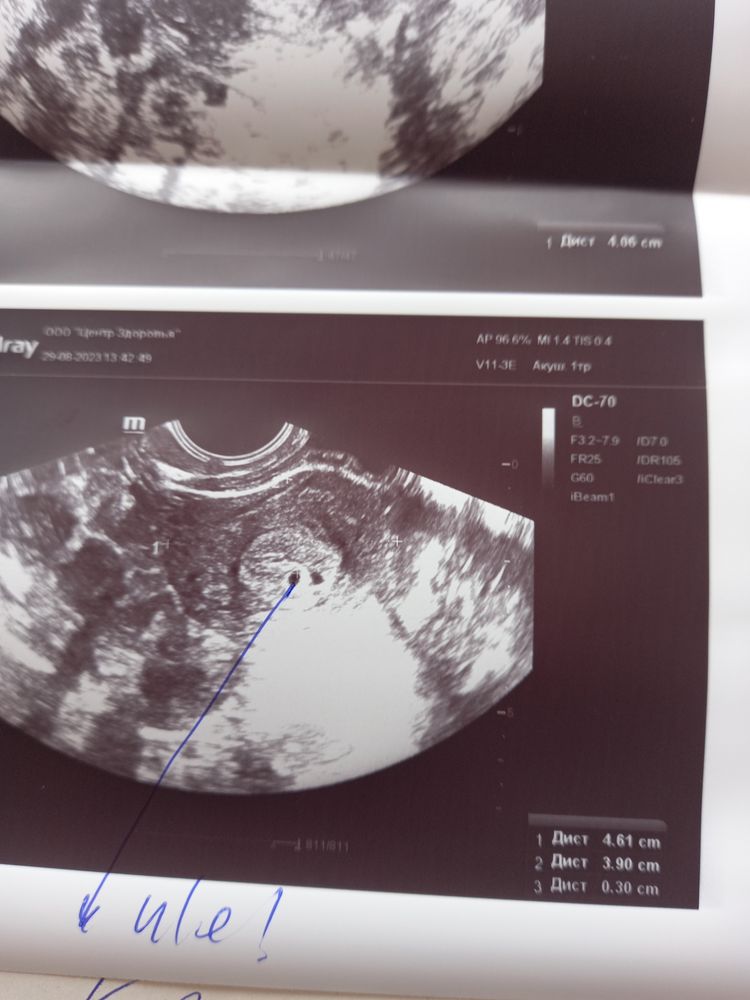

Хгч п.я.3мм

Девочки похоже ра 2 плодных яйца иль мне кажется. П.я.3 мм.при гхч 860 что думаете?

Вот мой последний график.када овуляция была я хз.капелька крови была 20числа 21 числа хгч был 68 23 числа 162 28числа 860 а узи сегодня 29числа последние месячные были 26